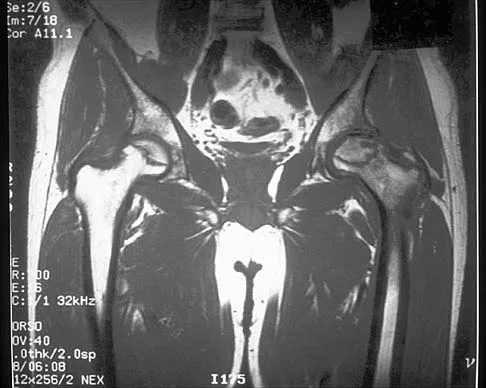

Question 22High Yield

A 20-year-old basketball player reports a 6-month history of right groin pain that radiates into his testicles with activities of daily living. He denies any history of trauma. Examination reveals tenderness about the groin, and he has full hip range of motion. The abdomen is soft. Radiographs are normal. Nonsurgical management has consisted of rest and physical therapy, but he continues to have pain. What is the next step in management?

Explanation